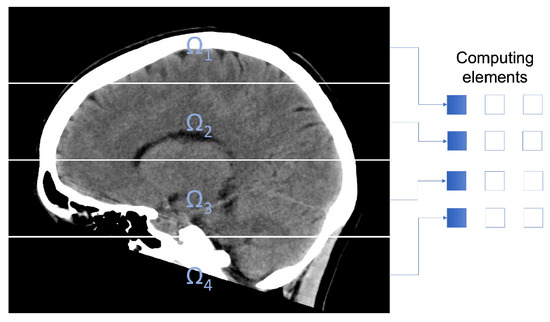

2.3. Parallel Fuzzy Filter

To reduce the computing times, a parallel method based on the described algorithm is introduced. In order to distribute the pixels of the medical image among the computing units in the parallel computer, the domain Ω of the image is split in P subdomains Ω i , i = 1 , P , being P the amount of computing units. This decomposition fulfills

Ω i Ω , i = 1 , 2 , , P Ω i = Ω , and Ω i Ω j = for i j .

Figure 1 exemplifies the subdomains utilized in the experimentation.

Figure 1. CT image decomposition using 4 subdomains.